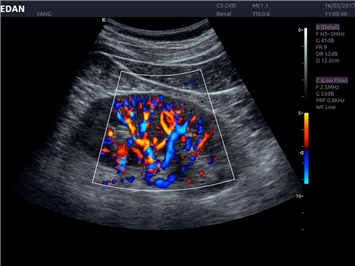

Трехмерная реконструкция ЦДК:

Да

Цветовой допплер:

Color 3D: